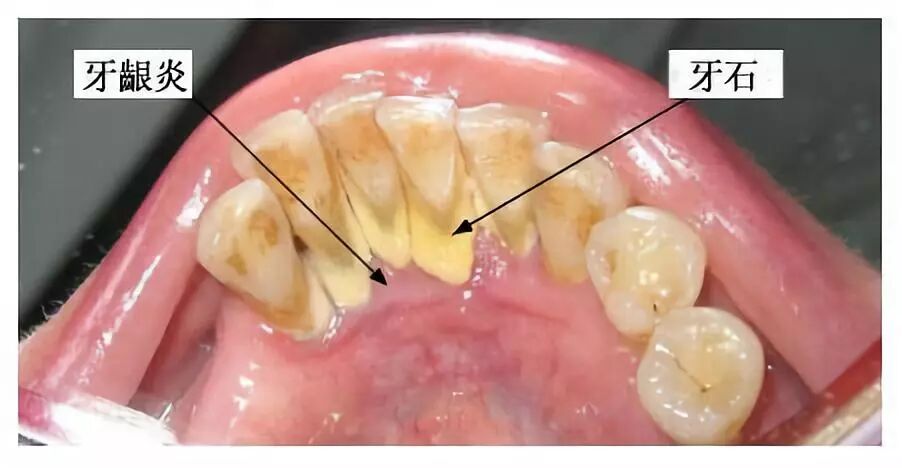

另外就是牙结石,牙结石起初是乳白色,但慢慢会随着牙龈出血、烟酒或喝咖啡等习惯变成黑褐色。

牙结石虽小但危害极大,如果不及时清除则会破坏牙周,刚开始时会牙龈红肿出血,但时间一长牙槽骨会“发炎”,然后造成“骨丧失”,就像大树和树根的关系。

如果你有牙龈出血或刷牙出血的现象,就要注意了,可能是牙龈炎,若不及时洗牙,可能演变成不可逆的牙周炎,甚至引发其他疾病。